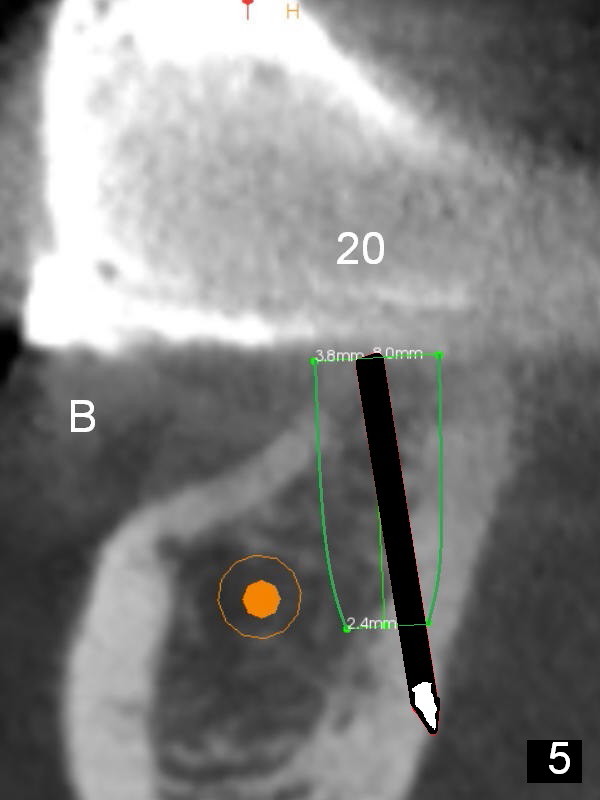

At the site of #20, osteotomy for the same implant is finished without sign of nerve injury or lingual plate perforation. To place the implant a little deeper, a 2 mm drill is used to deeper for another 2 mm. The latter also turns out to be hard. When it is done, perforation occurs, noticed first by the patient (Fig.4). The perforation is fixed with Osteogen plug (Fig.5 white area), while the implant is placed at the crestal level as planned.